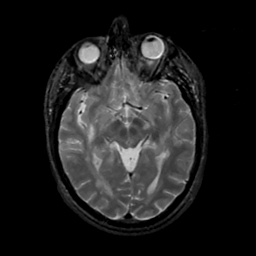

MR Study #14, June 2, 1991 -- Slice #22